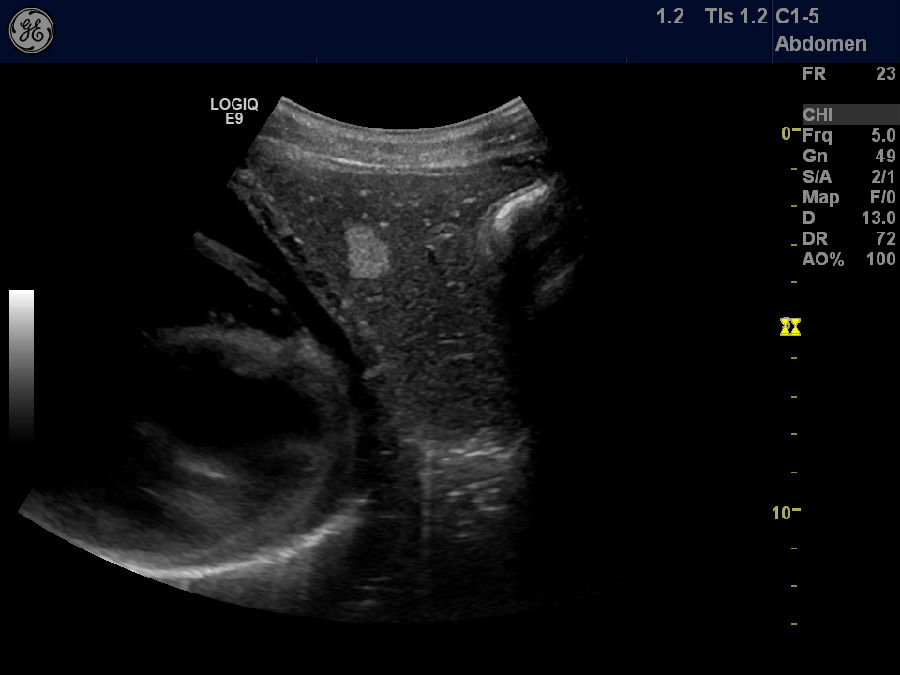

肝血管瘤

剑突下纵切,肝内高回声结节,血管瘤